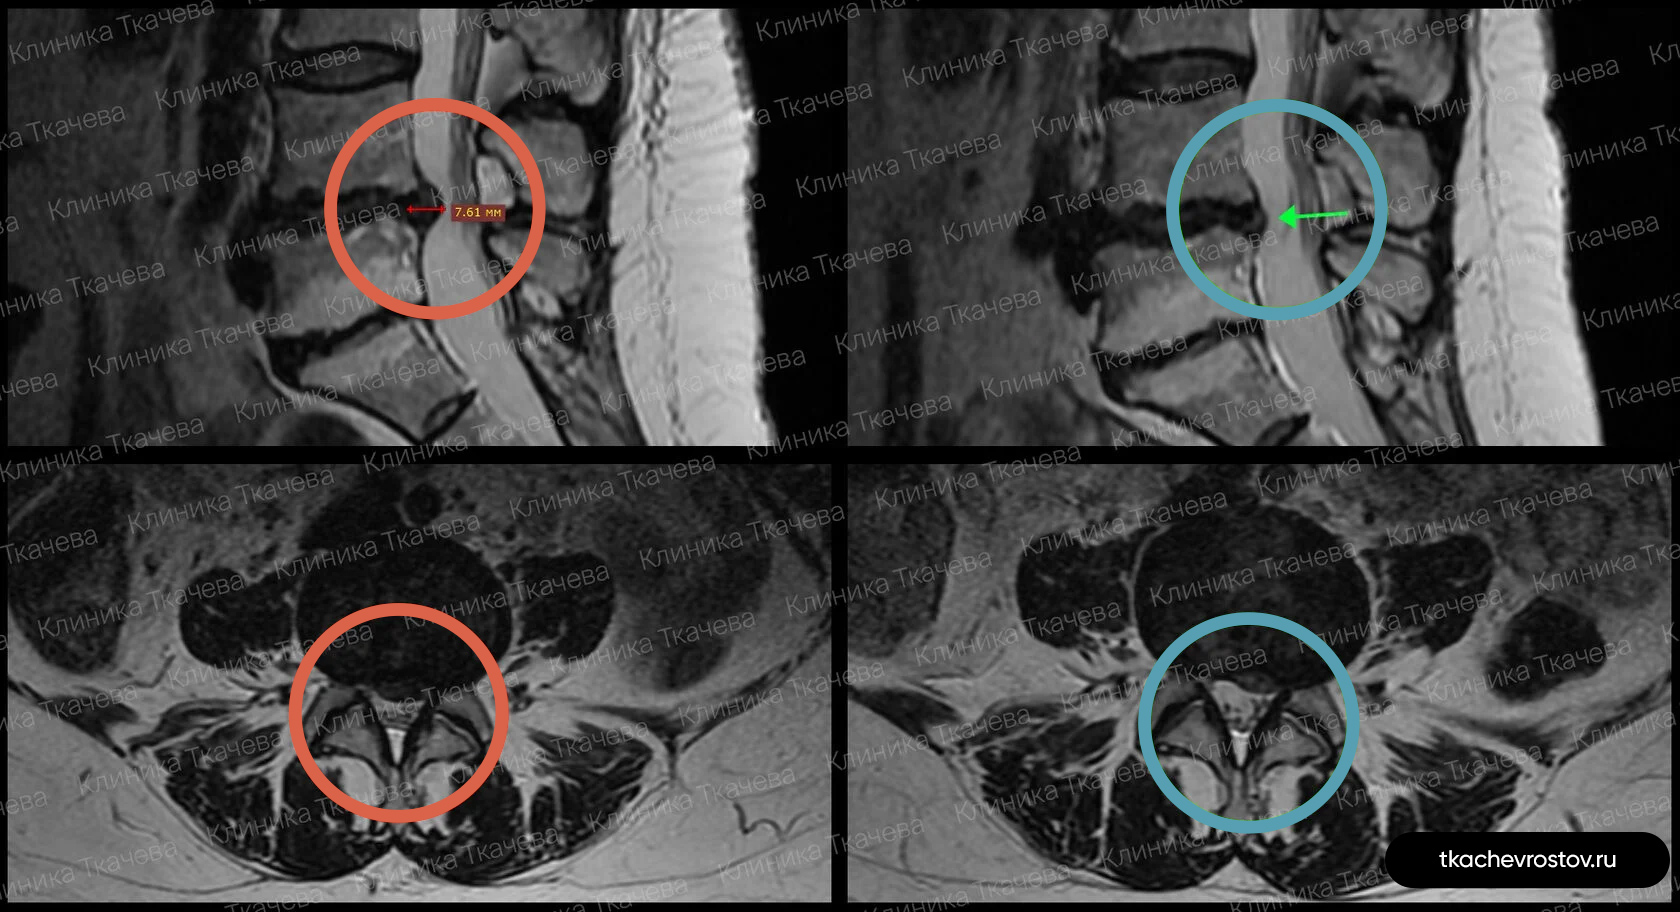

Грыжа в поясничном отделе L4-L5

Женщина. Грыжа в сегменте L4-L5 9 мм х 2 см. Невролог направлял на операцию, нейрохирург пугал отказом всех возможных систем жизнеобеспечения.

ДО:

- Боль в спине

- Онемение в левой ноге

- Снижение бытовой и социальной активности

ПОСЛЕ 1 курса:

✓ Наступила полная резорбция грыжи

✓ Наступило улучшения общего состояния.

ПОСЛЕ 2 курса:

✓ На 2022 всё стабильно.

Лечение грыжи заняло 5 месяцев. Было проведено 2 курса лечения.